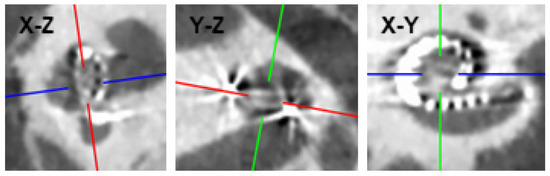

| Participant | Age at Implantation (Years) | Sex | Side | Etiology | Preoperative PTA (dB HL) | Hearing Preservation (%) | Length of Cochlear Duct (mm) | Electrode Array | Angular Insertion Depth (°) |

|---|---|---|---|---|---|---|---|---|---|

| P1 | 65 | Male | Left | Progressive SNHL, unknown cause | 83.75 | 57.1 | 36.2 | HiFocus Mid-Scala (Advanced Bionics) | 374° |